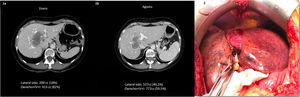

Presentamos el caso de una mujer de 55 años sin antecedentes de interés, diagnosticada histológicamente de CCI de 60×48×56mm localizado sobre la bifurcación del pedículo hepático, afectando los segmentos IV,V,VIII y en contacto directo con la vena hepática media sin diseminación extrahepática (fig. 1a). Inicialmente la cirugía necesaria era una triseccionectomía derecha; no obstante, el hígado remanente (SII-III) no tenía un volumen residual suficiente (200cm3 [18%]). Por ello, se realizó una terapia combinada de QT con gemcitabina-oxaliplatino y SIRT en dos dosis de 0,9 (80%) y 0,2 (20%) GBq a través de la arteria hepática derecha y de una rama del S4, respectivamente. A los 6 meses de la radioembolización y tras 12 ciclos de tratamiento quimioterápico se objetivó una discreta disminución de la lesión y una hipertrofia del remanente hepático de hasta 527cm3 (40%), lo que suponía un crecimiento del 160% (fig. 1b). Se calculó la funcionalidad del futuro hígado remanente mediante gammagrafía SPECT con Tc99 Mebofrenina, obteniendo un índice De Graaf de 2,1%/min/m2 e HIBA del 20%. La paciente en todo momento presentó una función hepática adecuada con valores normales de bilirrubina y enzimas hepáticas. Ante dichos resultados se propuso la resección quirúrgica.

1) Evolución tras tratamiento neoadyuvante. 1a) Fase venosa del TAC inicial, previo al tratamiento: gran masa hipodensa en disposición central en contacto directo con la vena hepática media. 1b) TAC postembolización: importante hipertrofia contralateral (S II-III). 2) Intervención quirúrgica: atrofia hepática derecha e hipertrofia contralateral, de los segmentos II-III.

La intervención se llevó a cabo 339 días tras el diagnóstico, objetivando una importante atrofia del hígado derecho e hipertrofia del sector lateral izquierdo (fig. 1.2). Se realizó una triseccionectomía derecha con caudectomía y resección de la vía biliar extrahepática con linfadenectomía. La reconstrucción biliodigestiva se llevó a cabo con una doble hepaticoyeyunostomía en Y de Roux. Se procedió a la toma de presiones portales al inicio y final de la cirugía demostrando un gradiente de 10mmHg entre vena porta y vena cava inferior suprahepática, por lo que se decidió no actuar sobre el flujo portal. La anatomía patológica definitiva fue informada de CCI pobremente diferenciado (G3) con márgenes libres sin infiltración perineural ni vascular (pT1bN0).